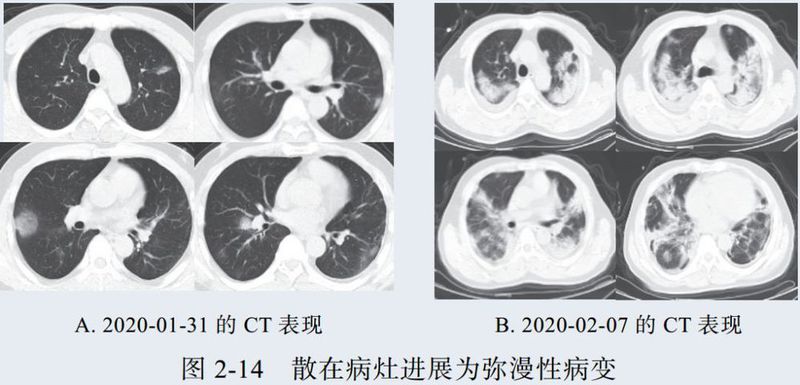

二、进展期征象

新冠肺炎大多数病例进展迅速,复查 CT 影像发生明显变化。

表现为病灶数目明显增多,范围明显扩大,密度增高,病灶分布由外周向中央推进。

根据既往 SARS 病理学机制,提示为肺泡腔内聚集大量细胞渗出液、间质内血管扩张渗出;肺泡连通起来形成融合态势(图 2-11)。